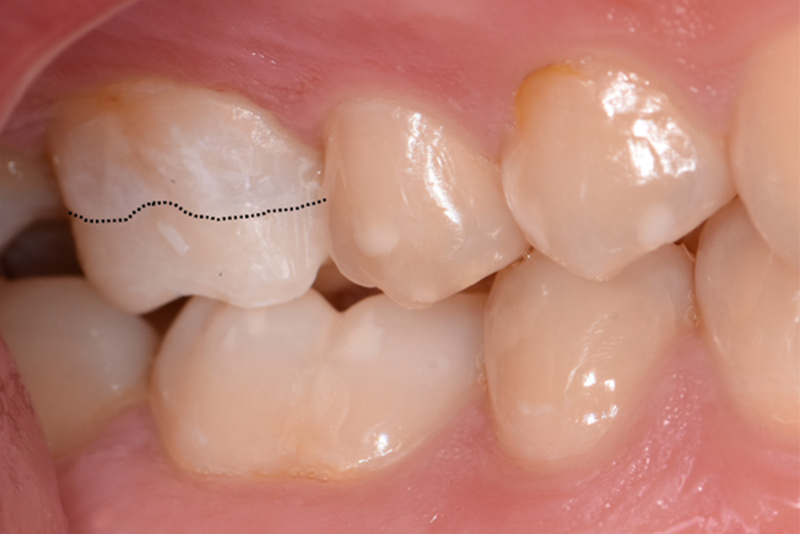

Les atteintes légères sont les plus simples à prendre en charge. L’éruption partielle de ces dents permet un accès favorable pour la réalisation de restaurations, notamment collées (Fig. 02), réhabilitant la fonction masticatoire et selon les cas l’esthétique du sourire.

Fig. 02 : collage d’un overlay sur 16 chez un patient atteint de DPE. Tracé du niveau initial des cuspides vestibulaires.